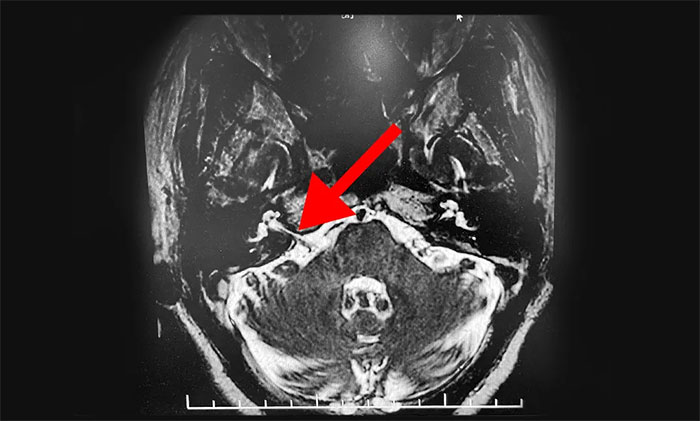

▲患者小脑血管与面神经根关系密切

头颅磁共振检查示,患者桥小脑角血管与面神经根关系密切。结合患者病史及相关检查,可明确诊断。